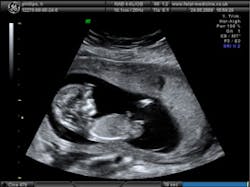

Intelligent Ultrasound's 3-D fusion ultrasound software aligns overlapping 3-D ultrasound scans and produces a composite image reconstruction that affords an increased field-of-view and improved anatomical definition when compared to a conventional 3-D ultrasound scan.

The first version of the ultrasound software for use in echocardiography is expected to be available for sale within six months. Further versions are being developed for stress-echocardiography, obstetrics and ultrasound-guided surgery.